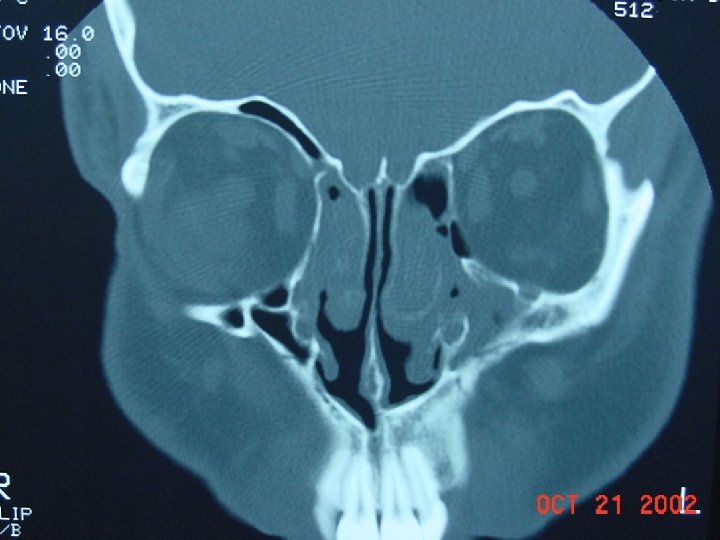

Diagnosis • Based on clinical signs and symptoms • Physical Exam: Palpate over the sinuses, look for structural abnormalities like DNS. • X-ray sinuses: not usually needed but may show cloudiness and air fluid levels • Limited coronal CT are more sensitive to inflammatory changes and bone destruction

Coronal computed tomographic scan showing ethmoidal polyps. Ethmoid opacity is total as a result of nasal polyps, with a secondary fluid level in the left maxillary antrum.